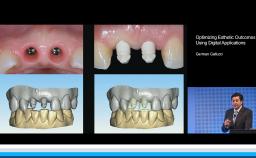

Treatment Outcomes and Continuing Care

Complications in Regeneration and Reconstruction

This lecture reviews in detail the various defects encountered in clinical practice that may need regenerative procedures for hard and soft tissue augmentation. The presentation is supported with excellent visual aids that illustrate how these defects can be reconstructed for prosthodontically driven implant placement. It also addresses how to prevent complications in regenerative and reconstruction procedures as well as the predominant treatment options to manage these complications. Clinical outcomes are supported by reference to several studies and clinical recommendations from the 4th ITI Consensus Conference.